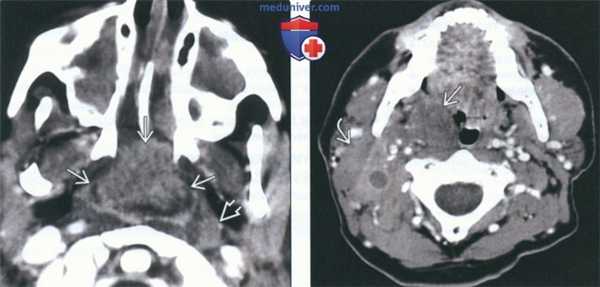

(Слева) КТ с КУ, аксиальная проекция. Пациент с неходжкинской лимфомой. В заглоточном пространстве, медиальнее правой внутренней сонной артерии определяется крупное новообразование, равномерно накапливающее контрастное вещество. Жировая клетчатка окологлоточного пространства смещена вперед и в латеральную сторону.

(Справа) КТ с КУ, аксиальная проекция, другой пациент с неходжкинской лимфомой. В левой части заглоточного пространства имеется крупный гомогенный лимфоузел овальной формы без признаков некроза. Левая внутренняя сонная артерия смещена назад и в латеральную сторону. Околоушные лимфоузлы также несколько увеличены.

2. КТ при неходжкинской лимфоме заглоточных лимфоузлов:

• КТ с КУ:

о Обнаружить при КТ может быть сложно, особенно если размер лимфоузлов невелик

о Округлое образование в ЗГП, неинтенсивно накапливающее контрастное вещество:

- По сравнению со здоровыми лимфоузлами захватывает контраст менее интенсивно (до лечения)